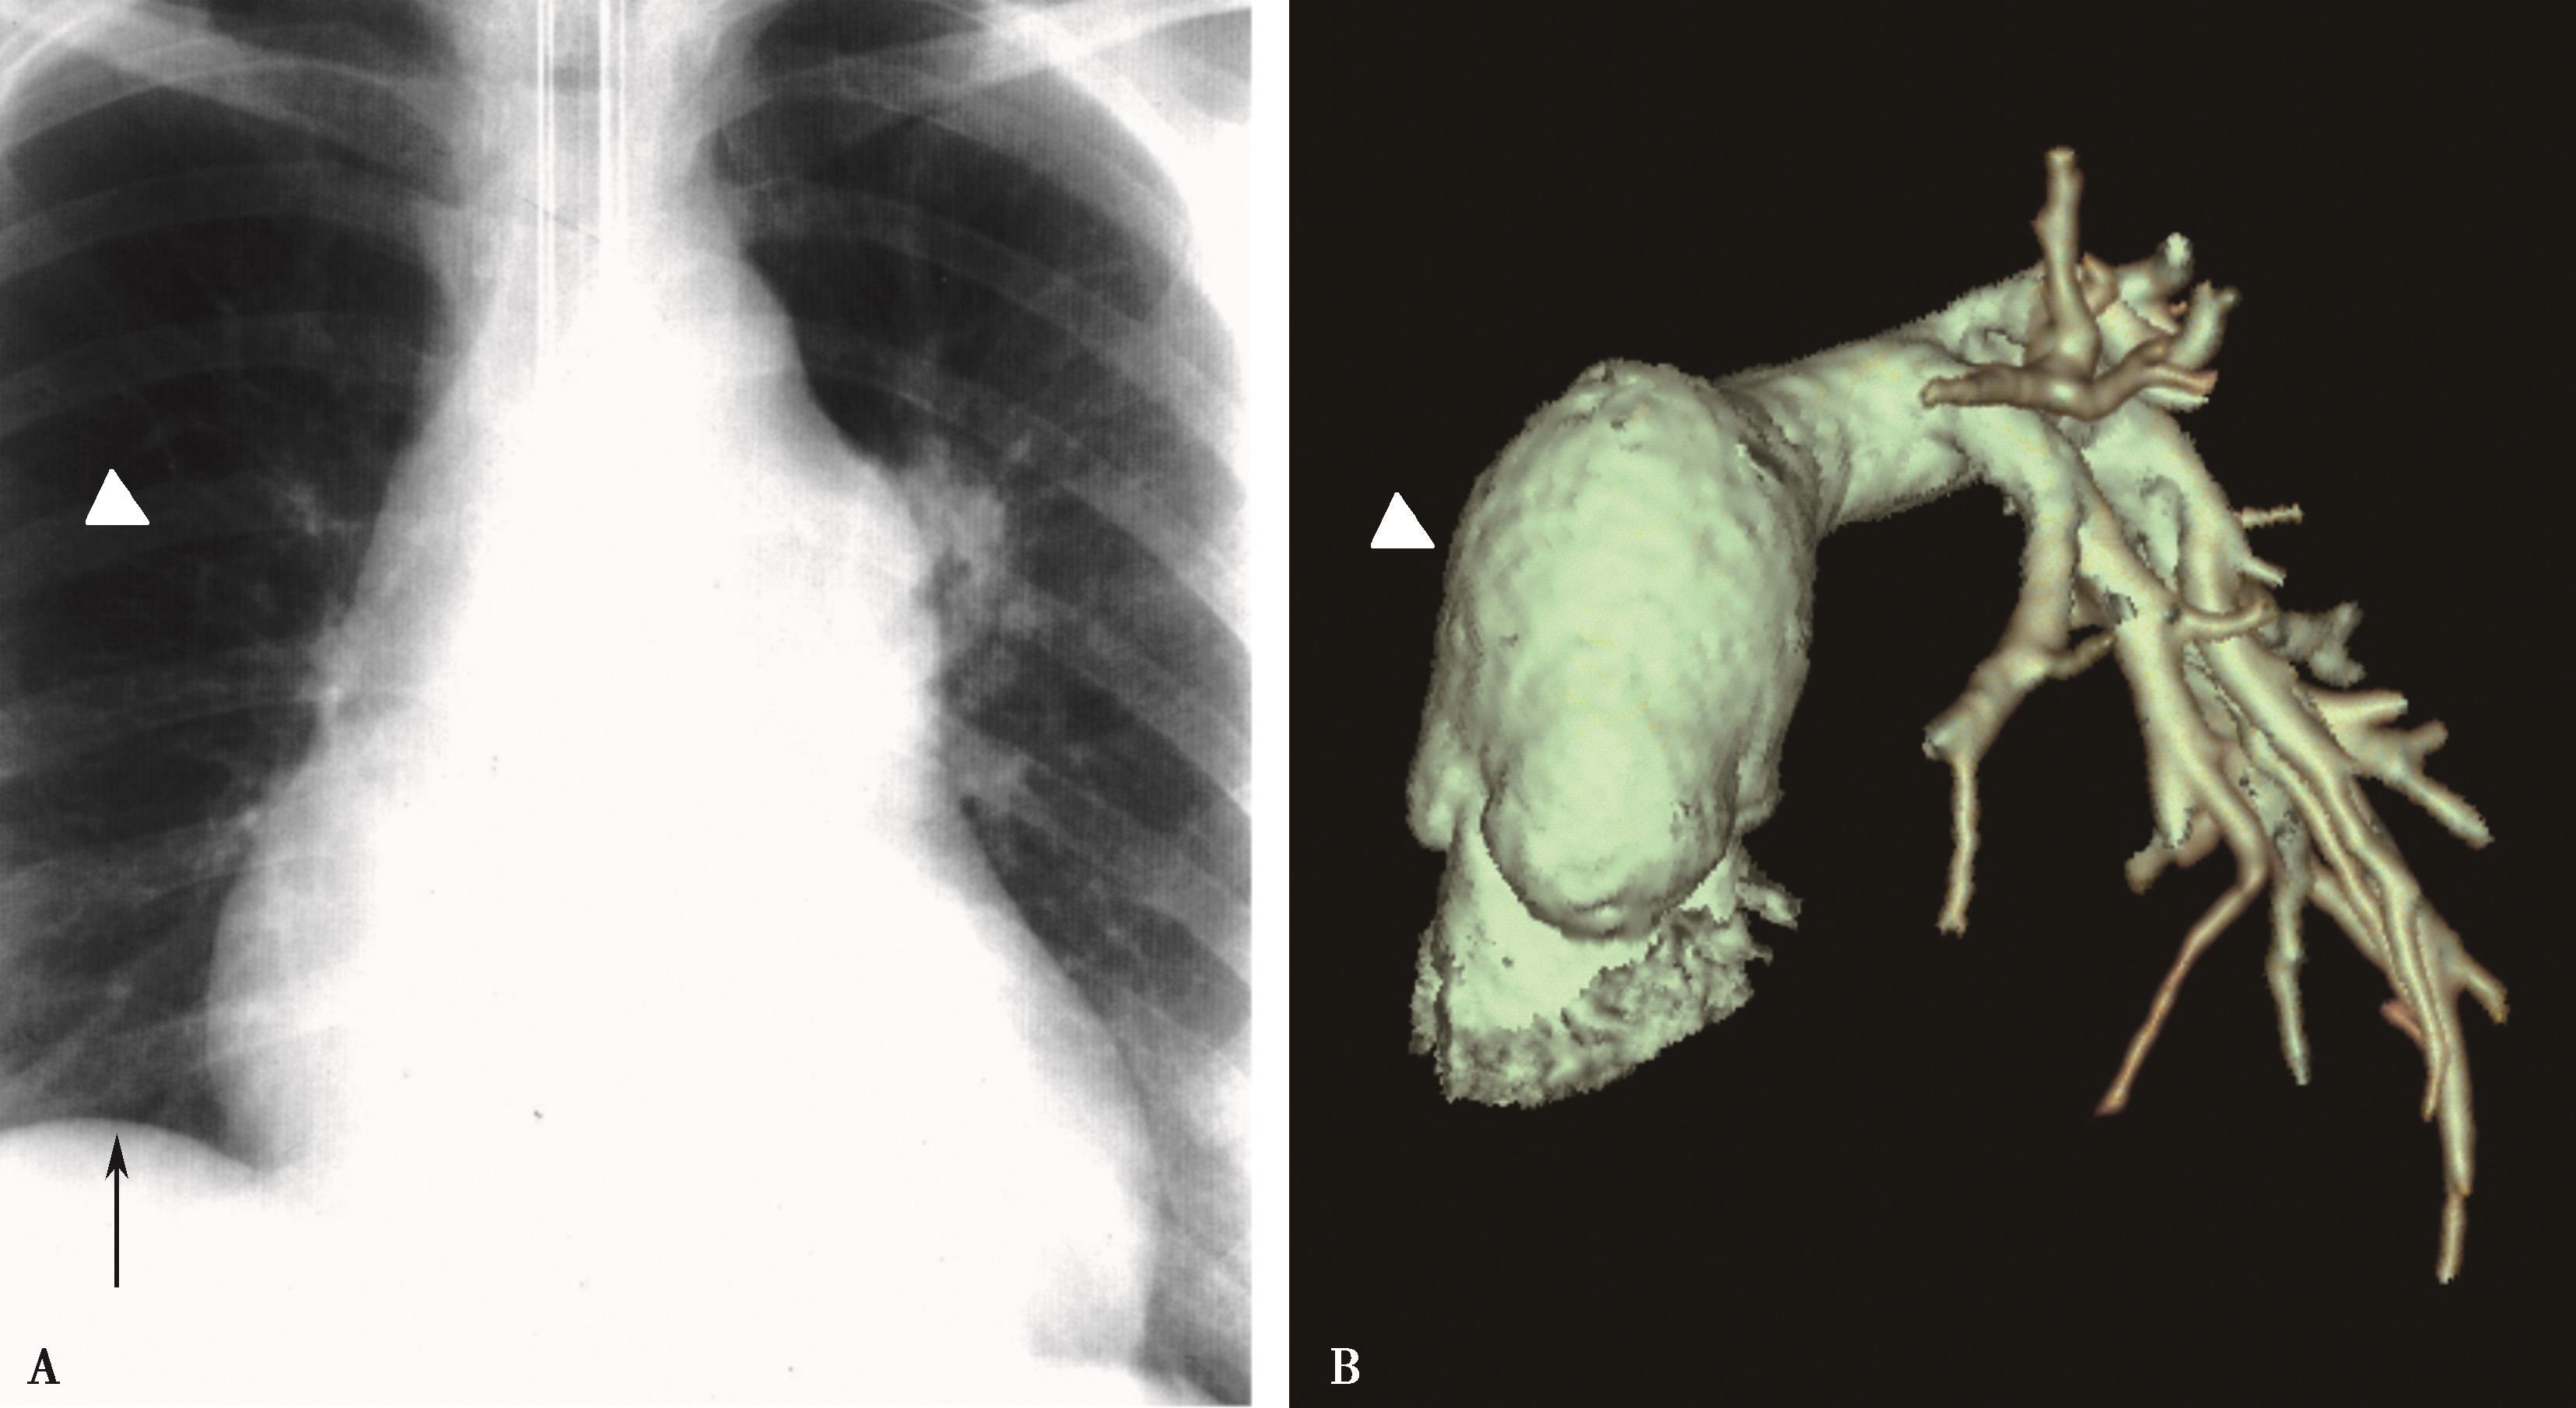

图7-2-4 女,37岁,大动脉炎(肺动脉型),右肺动脉重度狭窄。右侧肺血减少

A.心脏远达,右肺血减少,右心室增大;B.CTPA三维重建(VR),示右肺动脉重度狭窄(↑)